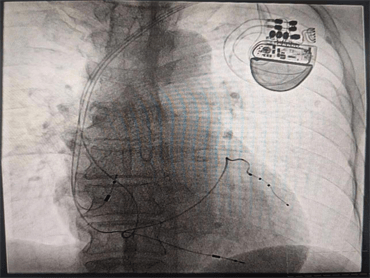

8月9日晚,心血管内科九病区崔旭辉主任团队成功开展了CRT-P(简称三腔起搏心脏再同步化起搏器)。该手术成功实施,为此类患者的治疗提供了一个新的保障,也标志着我科心力衰竭介入治疗技术又上了一个新台阶,具有重大意义。

由于患者心功能差,身材消瘦,且情绪较为焦虑,术后易伴并发症,心血管内科九病区医疗团队针对该患者的情况进行术前讨论研究,护理团队采用叙事护理的方法解除了患者的焦虑情绪,在充分考量患者的个体因素后,经患者及家人同意,确定手术方案。术中,崔主任亲切的语言缓解了张大爷的焦虑,在平静的状态下成功将三个电极植入到右心房、右心室、左心室(冠状静脉分支远端)圆满完成了手术。术后,反复程控参数,达到起搏器工作状态最优化,复查心电图示QRS波恢复到107ms,明显变窄,患者心脏功能及症状较手术前显著改善,远期疗效在进一步观察中,将通过不断程控,优化心脏起搏器参数,达到更好的治疗效果,崔主任亲自为患者按时换药,术后切口愈合良好。通过护士长魏薇及护理团队的精心指导,张大爷术后的康复锻炼也非常顺利。

心脏再同步化治疗(CRT或者CRT-P)是近年来发展迅速的治疗心力衰竭患者的重要手段,它是将电极植入右心房、右心室及左心室三腔起搏,使左右心室同步激动,同步收缩,改善心脏功能,降低心力衰竭患者病死率,是心力衰竭者的新希望,是心力衰竭治疗史上一个里程碑的突破。